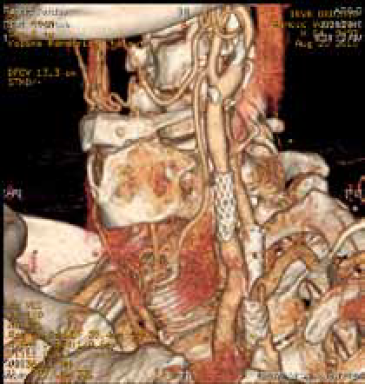

Multislajs CT angiografija supraaortičnih grana – restenoza zajedničke i unutrašnje karotidne arterije (desno) nakon standardne endarterektomije,

posle 19 godina.